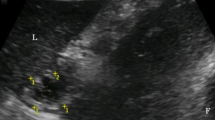

The microcirculation images of the mucosa and seromuscular layer at baseline and 240 min are shown in Fig. 3. For primary outcome comparison at 240 min, perfused small vessel density (PVSD) of the mucosa did not differ significantly between the Fluid DA and Norepinephrine DA groups [26.2 (3.2) vs 28.9 (2.5) mm/mm2, P = 0.077]. Results of other exploratory variables are as follows. In repeated measures analysis, PSVD of the mucosa was lower in the DA group than in the LA and Norepinephrine DA groups (Fig. 4), but PSVD of the mucosa did not significantly differ between the DA and Fluid DA groups. Total small vessel density (TSVD) did not significantly differ among the four groups. At 240 min, TSVD and PSVD of the mucosa in the Norepinephrine DA group were higher than those in the DA group [TSVD 29.0 (2.5) vs 24.7 (2) mm/mm2, P = 0.011; PSVD 28.9 (2.5) vs 22.3 (4.2) mm/mm2, P = 0.001]. At 240 min, TSVD and PVSD of the mucosa did not differ significantly between the DA and Fluid DA groups [TSVD: 24.7 (2.0) vs 26.4 (3.2) mm/mm2, P = 0.545; PSVD: 22.3 (4.2) vs 26.2 (3.2) mm/mm2, P = 0.083]. At 240 min, TSVD of the mucosa did not differ significantly between the Fluid DA and Norepinephrine DA groups [26.4 (3.2) vs 29.0 (2.5) mm/mm2, P = 0.195]. In repeated measures analysis, StO2 of the mucosa was lower in the DA and Fluid DA groups than in the LA and Norepinephrine DA groups (Fig. 4). At 240 min, tissue oxygen saturation (StO2) of the mucosa was lower in the Fluid DA groups than in the Norepinephrine DA groups [48 (7) vs 57 (6) %, P = 0.02].

Microcirculation images of the terminal ileal mucosa and seromuscular layer. Microcirculation images of mucosa are shown in LA group (a), DA group (b), fluid DA group (c), and Norepinephrine DA group (d) at 240 min. Microcirculation images of muscular layer are shown in LA group (e), DA group (f), Fluid DA group (g), and Norepinephrine DA group (h) at 240 min. In the DA group, perfused small vessels were fewer in the intestinal mucosa (b) and seromuscular layer (f). Norepinephrine infusion could restore microcirculation in the intestinal mucosa (d). DA deep anesthesia, LA light anesthesia.

Measurement of intestinal microcirculation and tissue oxygen saturation

After a 15-min stabilization period, baseline microcirculation examinations for the mucosa and seromuscular layer was performed with a sidestream dark-field video microscope (MicroScan, Microvision Medical, Amsterdam, The Netherlands) and a tissue oxygen monitor (white light reflectance spectroscopy, moorVMS-OXY, Moor Instruments Ltd., Devon, UK). The time after the examination was set as 0 min, and the rats received treatment according to their grouping. Intestinal microcirculation was examined again at 120 min and 240 min.

Intestinal microcirculation parameters, including TSVD (less than 20 μm) and PSVD were analyzed using semi-automated analysis software (AVA 3.0, Academic Medical Center, University of Amsterdam, Amsterdam, Netherlands) according to the guidelines of microcirculation analysis27,28. At each time point, three continuous image sequences (10 s) were digitally stored for each measured site, and the data of the three images were averaged for obtaining the required statistics. Analyses were performed by a single investigator who was blinded to grouping. At each time point, StO2 was measured at three points of the intestinal mucosa and seromuscular layer, and the data of these points were averaged for statistical calculation.